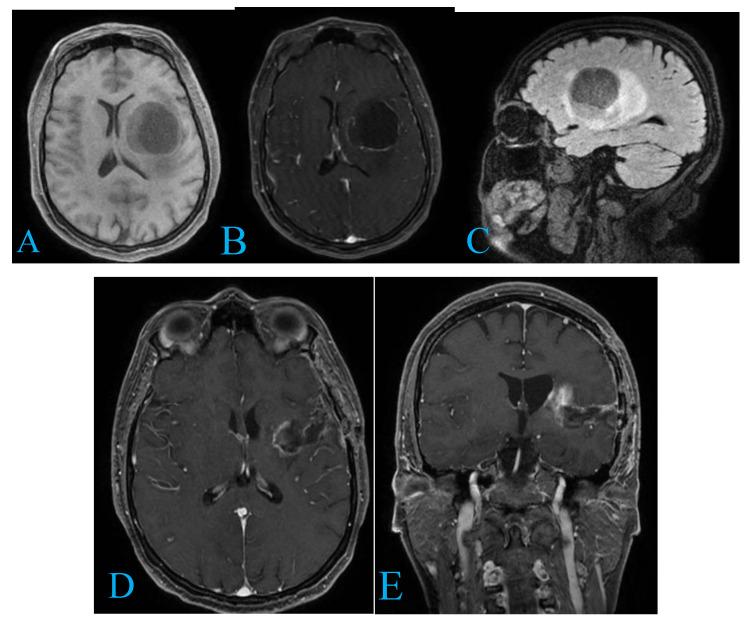

From 156 studies, 11 met inclusion criteria, highlighting advanced diagnostics, surgical strategies, and adjunct therapies for temporo-insular gliomas (TIGs). Gross total resection (GTR) was achieved in 39% of cases. Awake craniotomy enhanced functional outcomes, while temozolomide and radiotherapy improved survival. Challenges included ischemic complications and treatment resistance. Two patient cases underscored the complexity of TIG management and the importance of individualized approaches, achieving satisfactory resection with minimal deficits.

从156项研究中,11项符合纳入标准,突出了颞岛胶质瘤(TIGs)的先进诊断、手术策略和辅助治疗。39%的病例实现了大体全切(GTR)。清醒开颅手术改善了功能结局,而替莫唑胺和放疗提高了生存率。挑战包括缺血性并发症和治疗耐药性。两个患者病例强调了TIG治疗的复杂性以及个体化方法的重要性,在最小程度的功能缺损下实现了满意的切除。